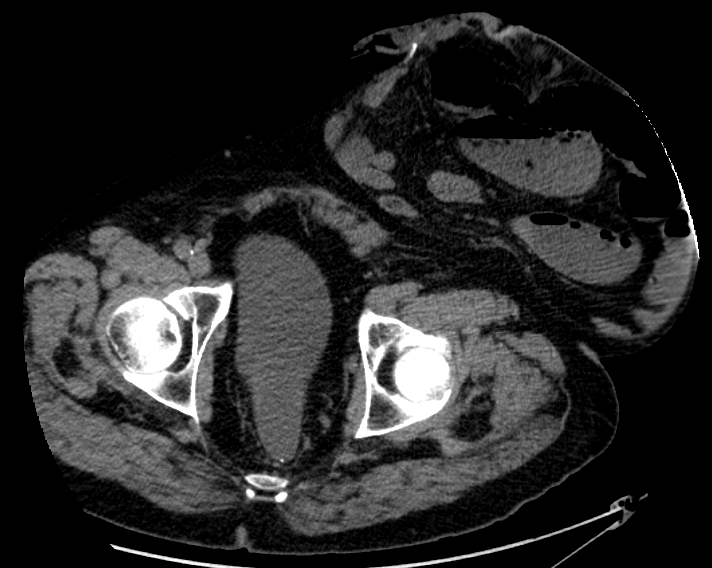

장루의 위치는 복부의 결장 어디에서든 발생할 수 있지만, 가장 흔한 위치는 대다수의 결장암이 발생하는 S상 결장 근처의 왼쪽 하단이다. 다른 위치로는 결장의 상행, 가로, 하행 부분이 있다.[4]